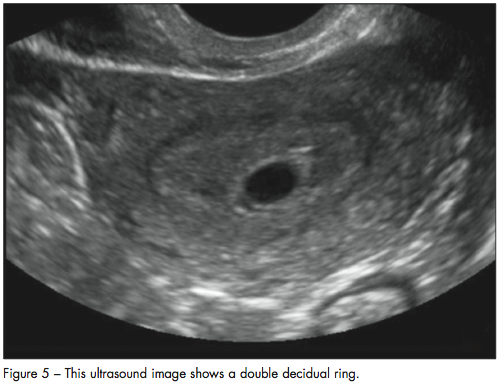

The double decidual ring, two echogenic rings around the gestational sac, is seen slightly later in pregnancy (Figure 5). In the radiology literature, it is considered highly reliable for the diagnosis of an intrauterine gestational sac and is pathognomonic for an early intrauterine pregnancy.43,44 Visualization of the double decidual ring helps differentiate the gestational sac from a pseudogestational sac. However, the double decidual ring has only a short window in which to be visualized and is not consistently seen.43,44 Furthermore, the double decidual ring can be difficult for clinicians who are not expert radiologists to identify correctly, leading to the incorrect diagnosis of an intrauterine pregnancy.42 Therefore, definitive evidence of an intrauterine pregnancy includes visualization of a yolk sac within the gestational sac, visualization of a fetal pole, or cardiac activity. This will exclude an ectopic pregnancy unless a heterotopic pregnancy is suspected.